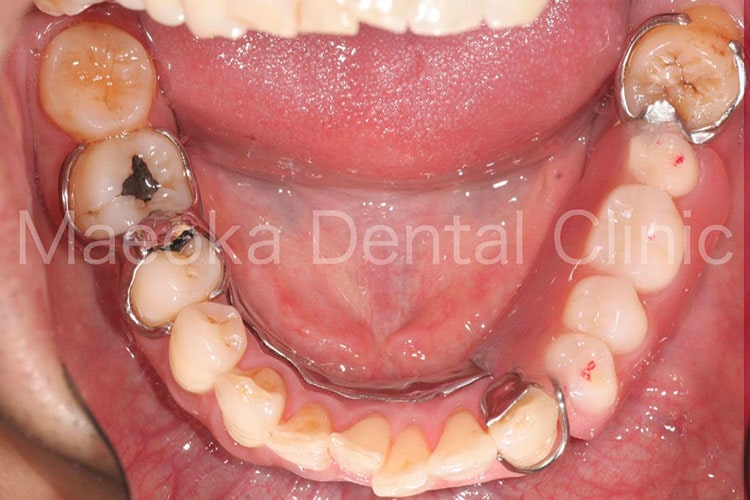

患者さんは54歳の男性の方で、「左下の入れ歯が噛むたびに痛くて違和感があるので診て欲しい。」という主訴で来院されました。

お口の中を拝見すると左下に義歯が装着されている状態で、上顎に偏った欠損が存在していることで左上の歯が噛む度に義歯を歯肉に押し込み、痛みを惹起していました。

患者さんと相談し、先ずは全顎的な歯周病の治療を行って歯肉を健全な状態に戻した上でインプラント治療によって固定式の治療を行うこととしました。

左下には4歯分の欠損があったため4本のインプラントを埋入することも検討しましたが、残っている骨の状態(厚みや高さ)を考慮し、最小限の2本だけ埋入し、被せ物を延長する形で対応しました。

結果として、インプラント治療のコストを抑えつつも清掃性を確保した欠損補綴を行うことができました。

治療の初期に患者さんのプラークコントロールが向上したことで、インプラントの箇所も日々綺麗な状態で管理されています。

治療前(下顎咬合面)

治療後(下顎咬合面)